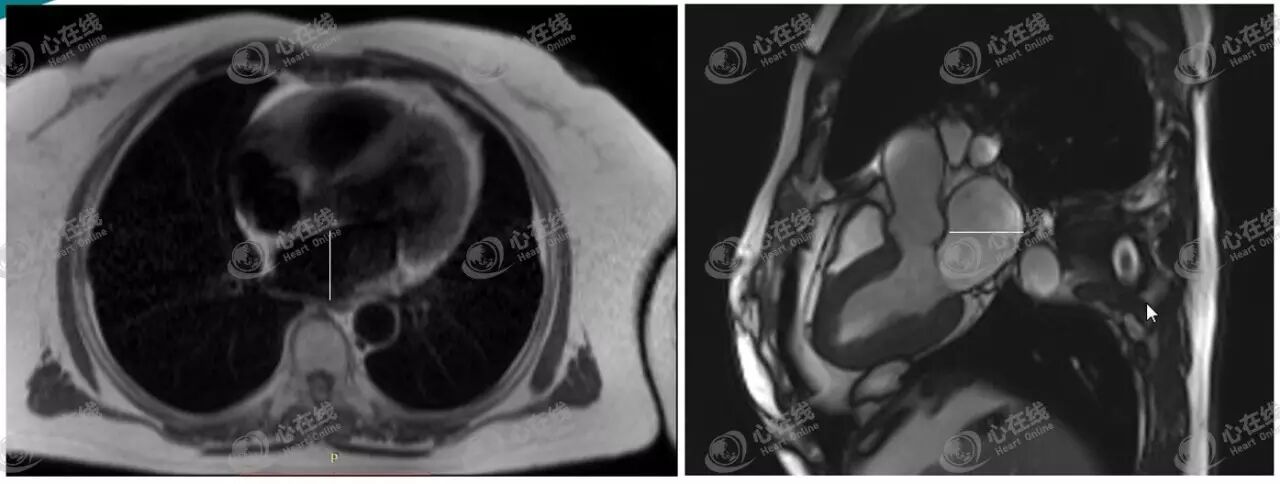

1、左房前后径测量

左房前后径一般在横轴位、三腔心或左室流出道平面测量。

如图7左图白线所示,在HASTE横轴位图像上,选择左房体部显示最大的平面,连接左房前壁与后壁的最大直线距离即为左房前后径。

如图7右图白线所示,在TrueFISP三腔心平面上,选择左室收缩末期左房体部中心平面的图像,连接左房前壁与后壁的最大直线距离即为左房前后径。

图7